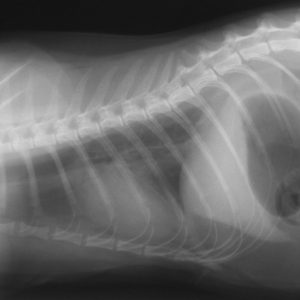

Рентгенограмма грудной клетки кошки в правой боковой проекции, малый объем плеврального выпота Рентгенограмма грудной клетки кошки в правой боковой проекции, малый объем плеврального выпота revtail2017-01-13T16:42:18+04:00